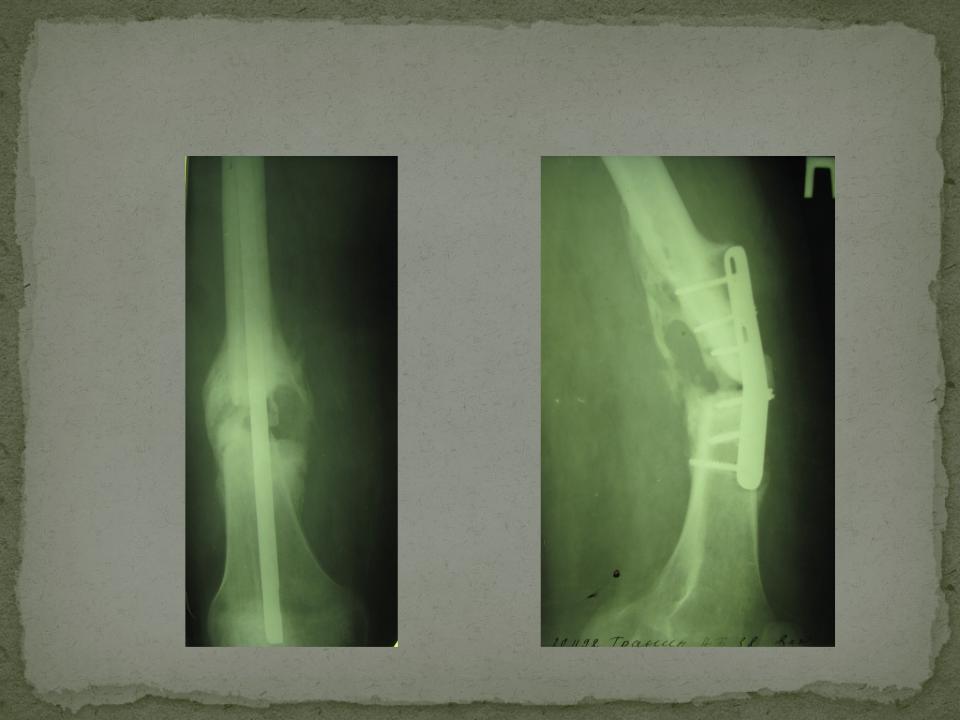

Рентгеновские снимки посттравматического остеомиелита челюсти: Медицинские случаи

Раздел: Образы вокруг